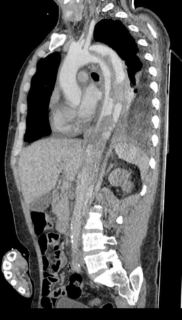

وأوضح بيان هيئة الرعاية الصحية، التدخل الجراحي تم على مرحلتين لمريض يبلغ من العمر 44 عامًا كان يعاني من انسلاخ بالشريان الأورطي النازل وتقرحات بقوس الشريان الأورطي وتجمع دموي بالشريان الأورطي الصاعد، حيث وصل المريض إلى قسم الطوارئ بالمستشفى في حالة حرجة يعاني من آلام شديدة بالصدر والظهر وارتفاع في ضغط الدم، وعلى الفور تم التعامل معه وإجراء الفحوصات اللازمة، ونقله للعناية المركزة للسيطرة على حالته ومنع تدهورها.

وتابع البيان، بناءً على التقييم الطبي للحالة تقرر إجراء تدخل مزدوج حيث تضمنت المرحلة الأولى إجراء عملية قلب مفتوح لاستبدال الشريان الأورطي الصاعد وإعادة توصيل شرايين الرقبة باستخدام شرايين صناعية، فيما شملت المرحلة الثانية تركيب دعامات مغطاة بالشريان الأورطي وقوسه باستخدام تقنية TEVAR وغلق الشريان تحت الترقوة باستخدام سدادة عبر القسطرة التداخلية تحت توجيه الأشعة التلفزيونية عن طريق المريء وتم تنفيذ التدخلين باستخدام أحدث التقنيات الطبية وبكفاءة عالية أسفرت عن تحسن ملحوظ في حالة المريض الذي غادر المستشفى بعد أسبوع من المتابعة الدقيقة وهو بحالة مستقرة الآن.

هذا، وقد تم إجراء العملية على يد نخبة من الكوادر الطبية بمستشفى طيبة التخصصي التابع للهيئة شملت كل من الدكتور محمد أبو منصور استشاري ورئيس قسم جراحة الأوعية الدموية والدكتور محمد عبد القادر استشاري ورئيس قسم جراحة القلب والصدر والدكتور سعيد عبد العزيز أستاذ جراحة القلب والصدر بطب القصر العيني والدكتور أحمد الجندي والدكتور شادي مجلي استشاريي جراحة الأوعية الدموية والدكتور محمد السيد استشاري أمراض القلب منفذ إيكو المريء والدكتورة سارة منصور والدكتور محمد شوقي مبروك استشاريي التخدير والدكتور محمد خميس والدكتور هيثم جميل استشاريي العناية المركزة، و بمعاونة فريق التمريض المتميز بالمستشفى في تناغم كامل يجسد جاهزية البنية التحتية والكفاءات البشرية المؤهلة داخل منشآت الهيئة للتعامل مع الحالات الدقيقة والمعقدة.